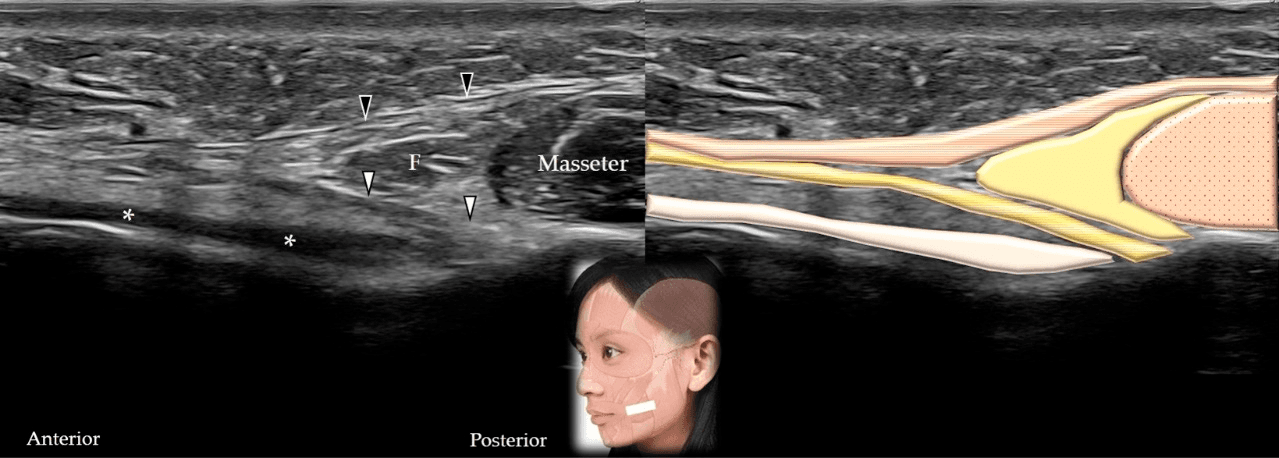

보툴리눔독소 - 교근(masseter)의 단축(A)과 장축(B)에 대한 초음파 스캔 및 도식적 표현입니다. 흰색 화살표와 회색 음영은 표재성 근건막계(super Figure 15. 교근(masseter)의 단축(A)과 장축(B)에 대한 초음파 스캔 및 도식적 표현입니다. 흰색 화살표와 회색 음영은 표재성 근건막계(superficial musculo-aponeurotic system), 검은색 화살표와 짙은 회색 음영은 이하선-교근근막(parotid-masseteric fascia), F와 노란색 음영은 지방(fat), 갈색 음영은 교근을 나타냅니다.